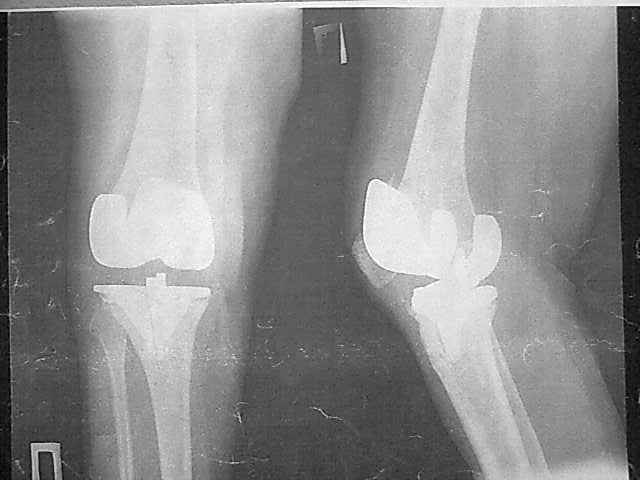

Уважаемые коллеги, прошу Вашего совета по тактике лечения. Женщина 1952 г.р., оперирована в

2006, в одной клинике установлен эндопротез правого коленного сустава, через год

Имя     : 1-06.11.06.jpg

Тип     : image/jpeg

Размер  : 24728 байтов

Описание: отсутствует

Url     : http://weborto.net:8080/pipermail/ortho/attachments/20090219/242fe889/attachment-0006.jpg